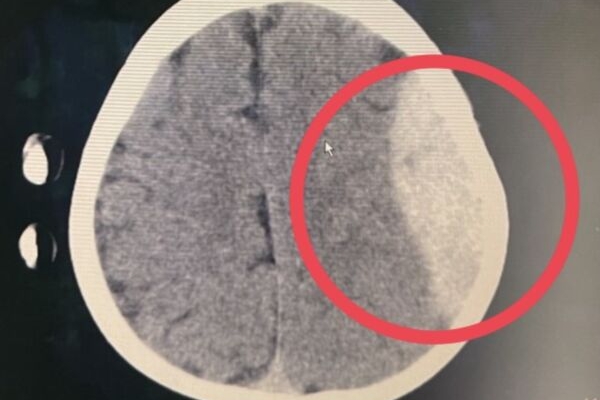

▲新店3歲男童從上舖樓梯跌落,經電腦斷層檢查發現顱內嚴重出血。

緊急搶命!新店一名三歲男童,日前在家中的上鋪跟姐姐玩耍,不小心從樓梯跌落,一開始家人未察覺異常,隔日清晨餵奶時,男童反覆嘔吐,趕緊送至急診經電腦斷層檢查後,發現顱內嚴重出血,緊急進行開顱手術才搶救回孩子性命。

▲左側顱內大面積出血。

陳俊勳醫師在接獲急診通知後,趕在男童瞳孔擴大前完成手術。術中發現顱骨出現深層裂縫,並有大量血塊壓迫腦部,醫療團隊即刻進行止血與減壓,歷經數小時手術順利完成,術後轉入兒童加護病房持續監測。